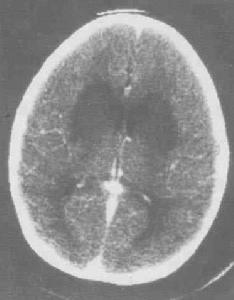

小儿病毒性脑炎--影像病前l-3周多有上呼吸道及胃肠道感染史、接触动物或昆虫叮咬史。患儿呈急性或亚急性起病,主要表现为脑实质损害及颅内高压。首发症状多有不同程度的发热、意识障碍,轻者出现表情淡漠、嗜睡,重者神志不清、谵妄、昏迷。较大儿童早期多出现精神障碍。颅内高压表现为头痛、呕吐、局限性或全身性抽搐,严重者引起脑疝,甚至呼吸、循环衰竭死亡。由于中枢神经系统受损部位不同而出现不同的局限性神经系统体征,如单瘫、双侧瘫、偏瘫、截瘫、多发性神经根炎、颅神经受损、小脑共济失调、不自主动作等。全部临床表现在起病3天至1周内出现,可持续1周至数月不等。婴幼儿早期阶段的症状包括: 医学百科网 | YxBaike.Com